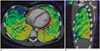

In the cardiovascular region, static dual-energy stress myocardial perfusion CT is more useful than coronary CT angiography for the detection of hemodynamically significant coronary artery stenosis by providing myocardial iodine distribution during the early arterial phase (25, 34). In cardioembolic stroke, dual-energy cardiac CT with dual-phase (arterial and 3 minutes delayed) intravenous injection of contrast agent can be used to accurately differentiate between left atrial appendage thrombi and circulatory stasis (35). Iodine map increases confidence in detecting endoleaks after aortic stent graft placement (36).